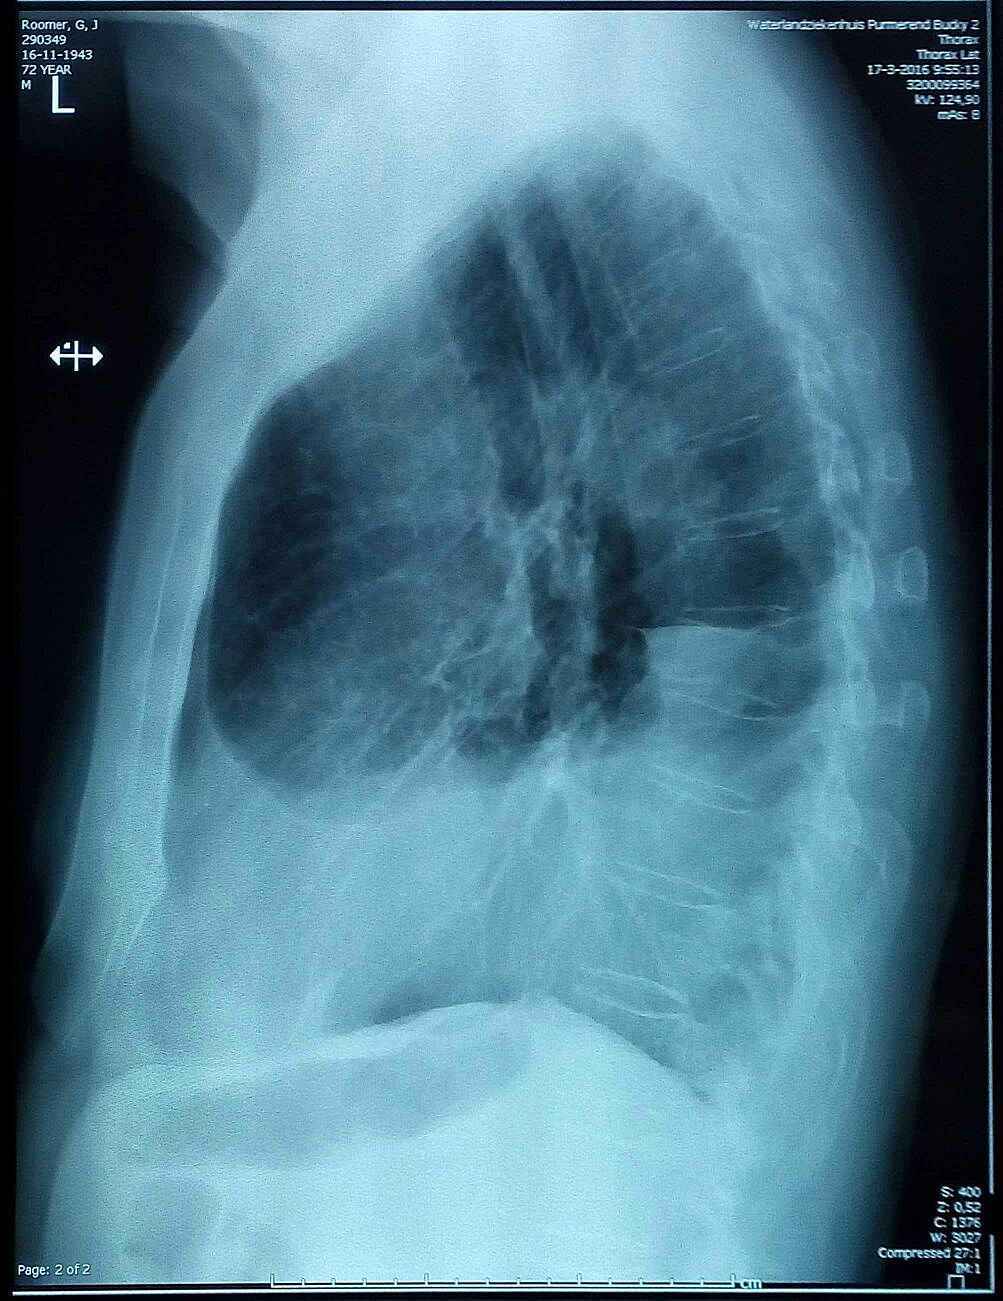

Half maart 2016